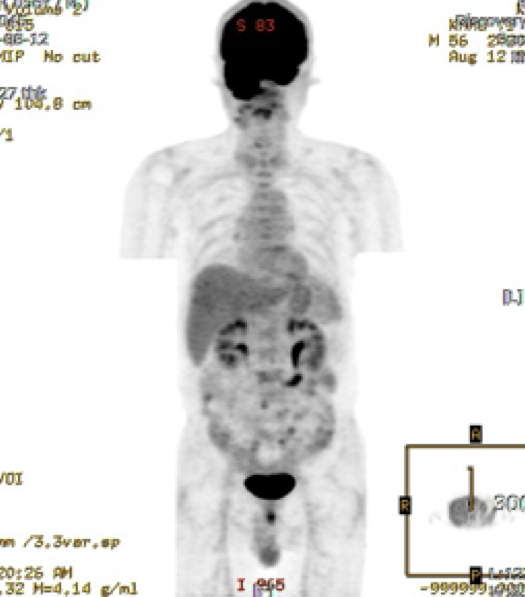

권고안 2-4 CT나 MRI 에서 임파절 병기 결정이 어려운 경우,임파절 병기결정의 정확도를 향상시키기 위하여 US-FNA 혹은 PET-CT 를 촬영할 수 있다.

권고안 2-5 구강암의 원격전이를 평가하기 위하여 PET-CT, 흉부 방사선 검사 (Chest PA) 그리고 Bone scan 등이 이용되어 진다.

권고안 2-6 구강암의 재발이 의심되는 환자에서 CT나 MRI로 확인되지 않거나 감별진단이 어렵다면 PET-CT가 시행될 수 있다.

- 양전자방출 단층촬영(PET/CT)

전산화단층촬영 |

양전자방출 단층촬영 |

전산화단층촬영

양전자방출 단층촬영